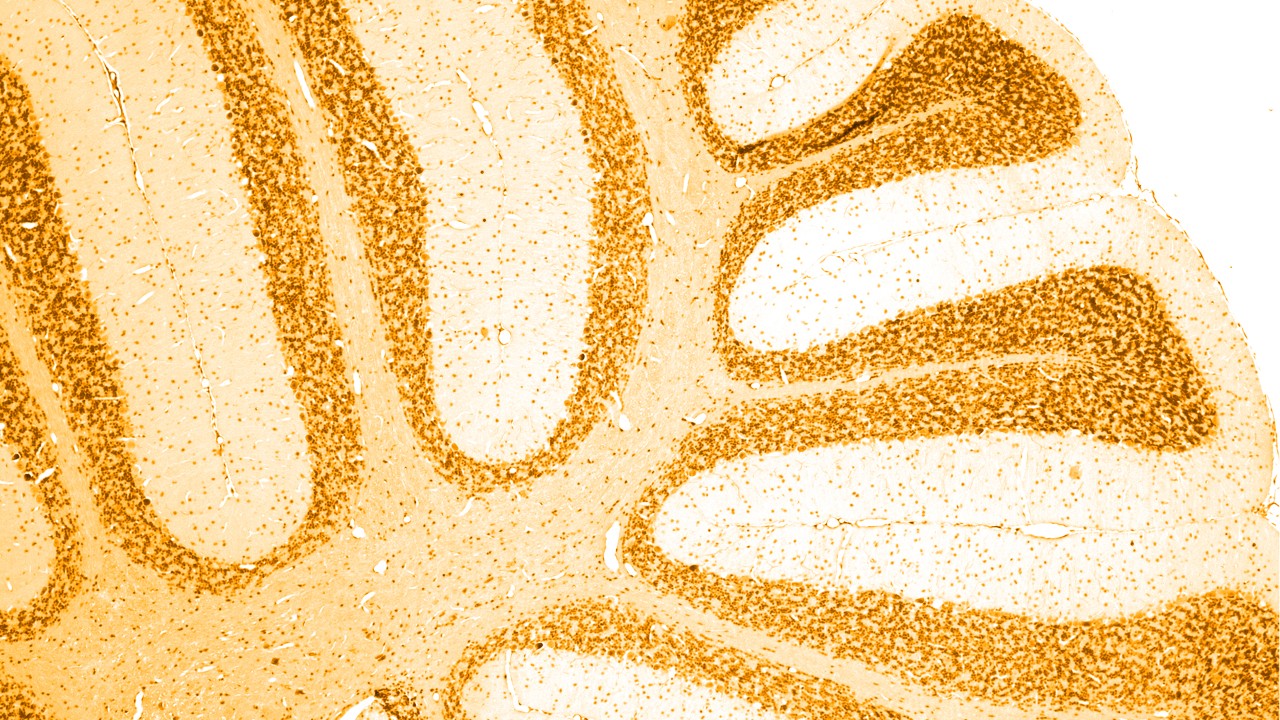

Er zijn verschillende oorzaken van dementie, waarvan de ziekte van Alzheimer de meestvoorkomende is en waarbij sprake is van een ophoping van abnormale 'amyloïde plaques' en 'tau-tangles' in de hersenen. Bij bepaalde andere vormen van dementie is er ook sprake van een abnormale ophoping van tau-eiwitten in de hersenen; als groep worden deze vormen ook wel aangeduid als 'tauopathieën'.